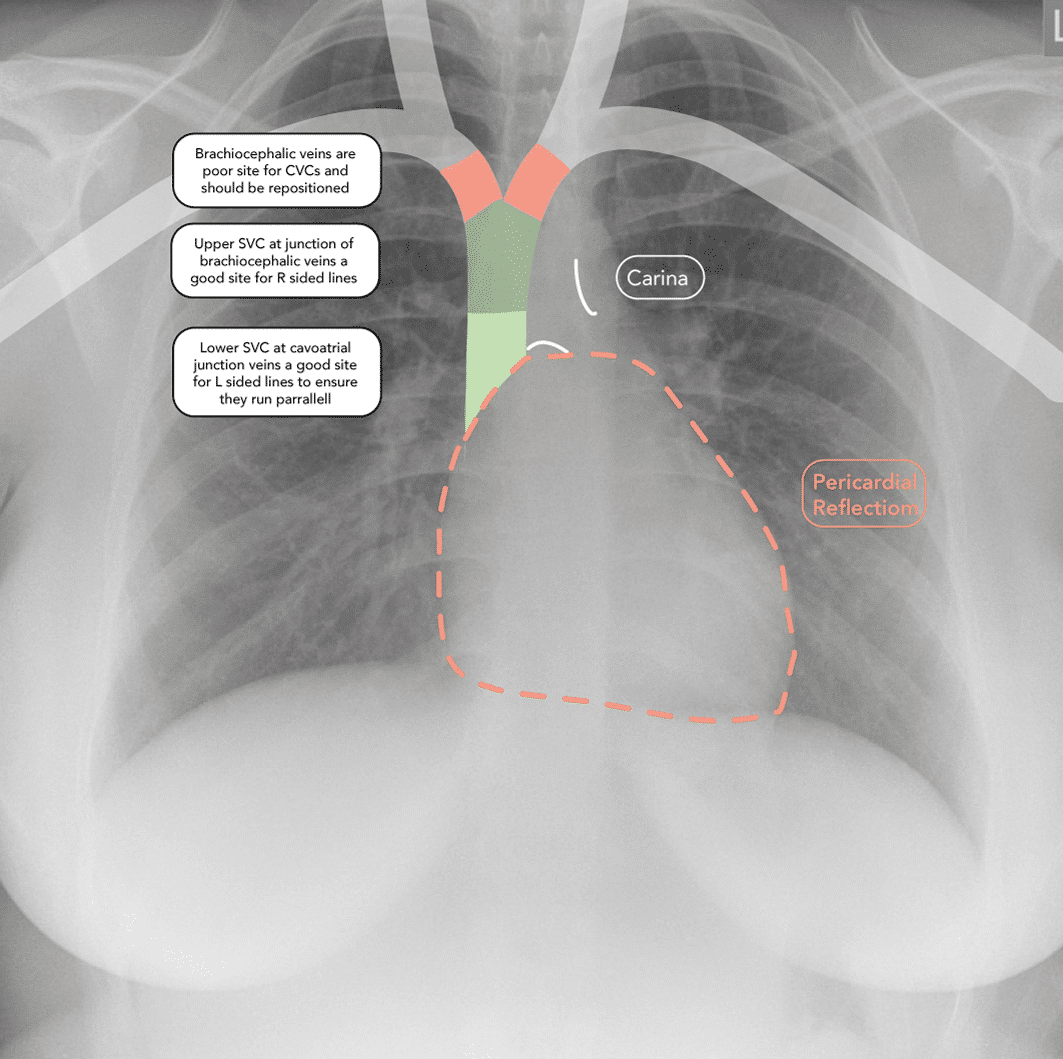

Central venous catheter tip position on chest radiographs Wright Bed Position For Central Venous Catheter central venous catheterization is an invasive medical procedure applied widely in pediatric and adult patients not only to measure. Central venous catheter (cvc) is a cannula placed in a central vein (e.g. Subclavian, internal jugular or femoral). temporary central venous catheters are inserted directly into the internal jugular vein, subclavian vein, or common femoral vein,. Centrally inserted central. Bed Position For Central Venous Catheter.